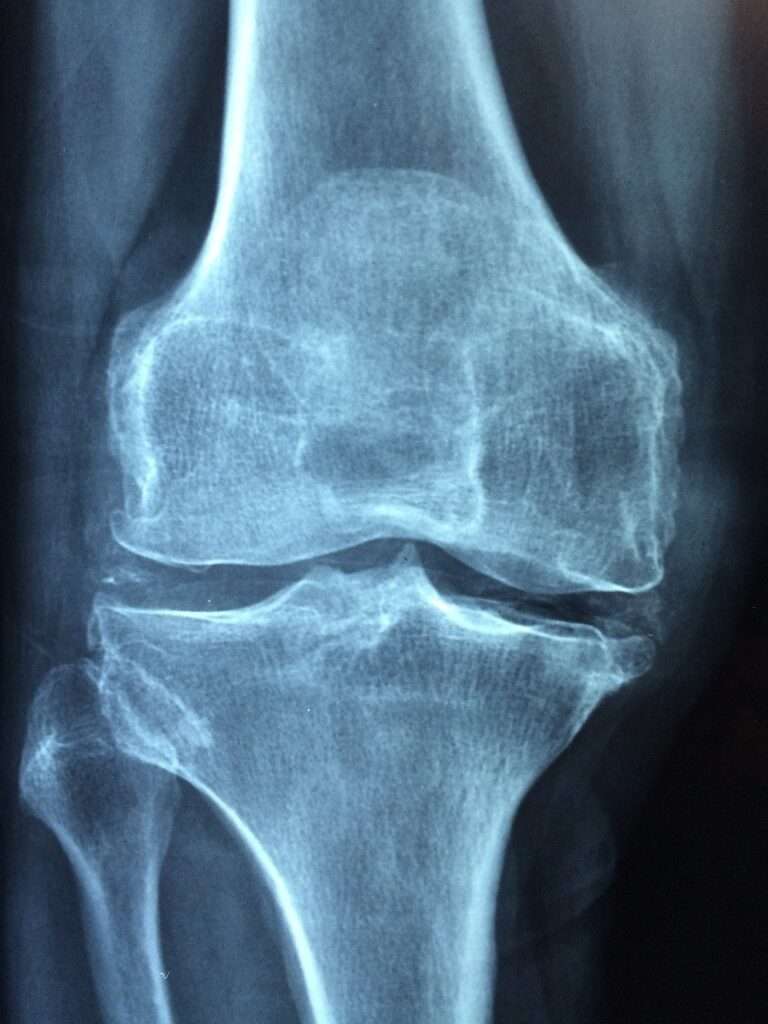

Osteoartritis

La osteoartritis, también conocida como artrosis, es la forma más prevalente de enfermedad articular a nivel mundial y está estrechamente asociada con el proceso de envejecimiento. A medida que las…

¿Qué es la osteoartritis?

Concepto Las articulaciones están constituidas por un conjunto de formaciones anatómicas que unen dos o más huesos. La osteoartritis es una enfermedad articular crónica degenerativa con componente inflamatorio, caracterizada por degeneración y pérdida progresiva…